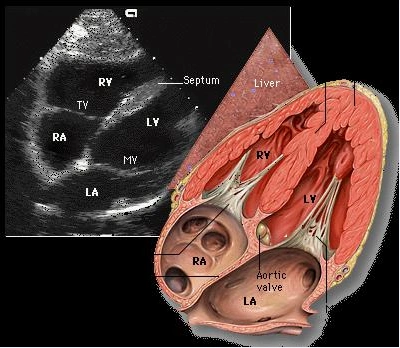

4声窗7切面搞定急诊超声心动图:由浅入深学tte|急诊"心"事

二维超声心动图常用切面及选择